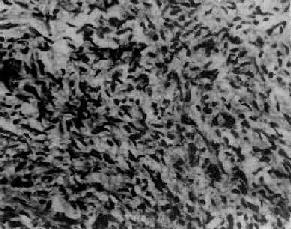

图13-21 卵巢泡膜细胞瘤

在卵巢泡膜细胞样瘤细胞中混杂一些空泡状黄体化细胞

肉眼观,绝大多数为单侧,中等大小,与残留的卵巢组织界限清楚,但无包膜,质硬。切面实性,可有小囊,也有多房者。瘤组织因含脂质而呈浅黄色,间有灰白色纤维组织或类似纤维瘤的旋涡状结构。镜下,瘤细胞形态与正常泡膜细胞相似,胞体形态肥胖呈梭形,胞浆丰富淡染(图13-21)。细胞核卵圆形,无核分裂像。瘤细胞排列紧密,形成宽阔的束带状,呈不规则交错分布或漩涡状排列,其间被大小不等的间质结缔组织条索所分隔。用特殊染色法可见泡膜细胞内含有丰富的类脂质物质,可与纤维瘤鉴别;用银染色法可见网状纤维围绕每个细胞,此与粒层细胞瘤时出现于整个细胞团周围者不同。